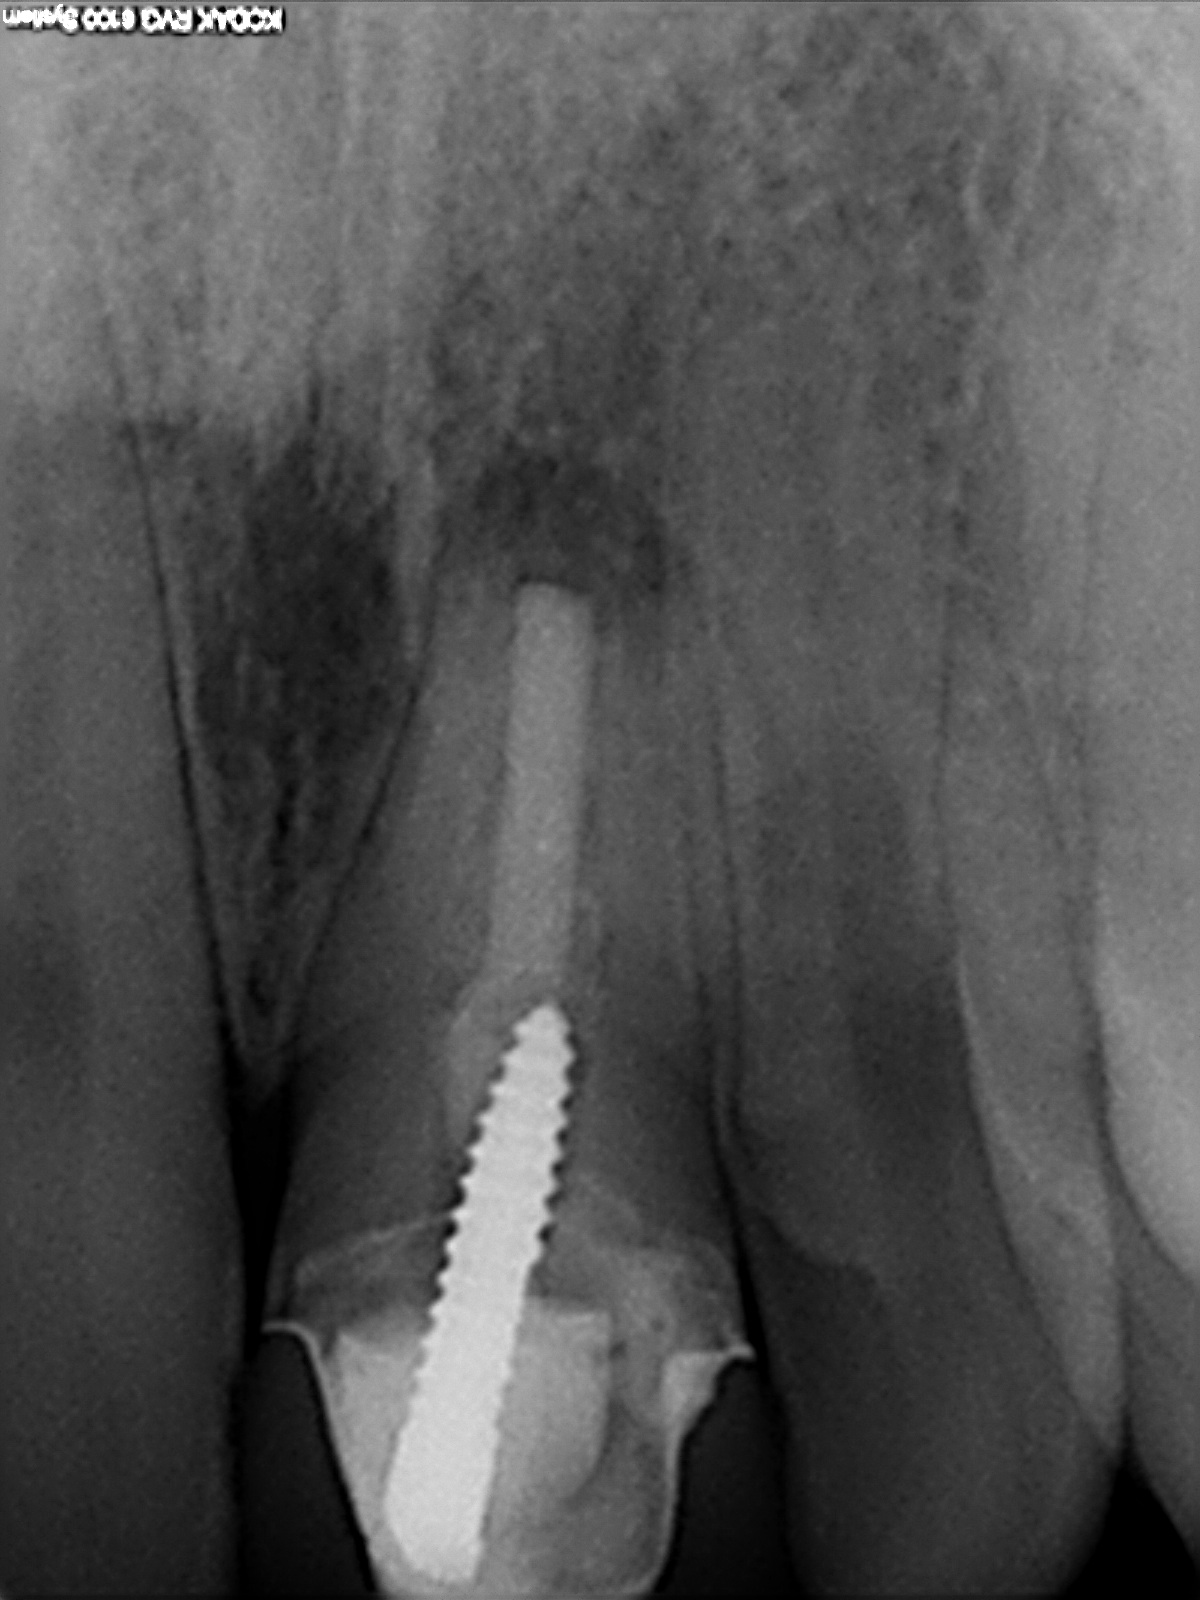

Fraktur?